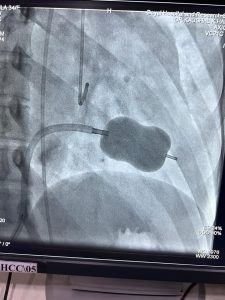

जोधपुर। गोयल हाॅस्पिटल, रेजिडेन्सी रोड पर गत 31 मई को तिंवरी गाँव निवासी 34 वर्षीय एक महिला लगभग 3 साल से श्वास फूलने, चलने पर थकान होने व धड़कन बढ़ने की श्किायत के साथ OPD में दिखाने आई। वहाँ पर गोयल हाॅस्पिटल के वरिष्ठ ह्दय रोग विशेषज्ञ डाॅ. कौशल कुमार हरलालका ने मरीज की जाँच एवं ईको-कार्डियोग्राफी करने के बाद पाया कि मरीज के ह्दय के बाँयी तरफ का वाल्व (Mitral Valve) सिकुड़ा हुआ है। डाॅ. कौशल कुमार हरलालका ने बताया कि सामान्यतः इस Mitral Valve की Size 4 से 6 cm square होती है, जो कि इस मरीज में 0.9 cm ही पायी गई। डाॅ. कौशल हरलालका ने मरीज के रिश्तेदारों से बातचीत कर मरीज को भर्ती कर बेलून ऑपरेशन (BMV-Balloon Mitral Valvotomy) कराने की सलाह दी। मरीज के रिश्तेदारों की सहमति के बाद डाॅ. कौशल हरलालका ने मरीज को भर्ती करके ठडट ऑपरेशन किया जो कि पाँव की नस से एन्जियोग्राफी की तरह किया जाता है। इस तकनीक में मरीज को बेहोश करने की भी जरूरत नहीं पड़ती व मरीज को 24 से 36 घण्टे के अन्दर डिस्चार्ज करके घर भेज दिया जाता है।

गोयल हाॅस्पिटल के डायरेक्टर डाॅ. आनन्द गोयल ने बताया कि सामान्यतः Valve के ऑपरेशन ओपन हार्ट सर्जरी से होते है। जिसमे 1 सप्ताह तक मरीज को अस्पताल में रहना पड़ता है एवं मरीज के ह्दय में कृत्रिम वाल्व लगाया जाता है। किन्तु इस आॅपरेशन मंे डाॅ. कौशल हरलालका ने मरीज में Balloon से BMV तकनीक का उपयोग करके मरीज को तुरन्त राहत पहुँचाई एवं मरीज के नेचूरल वाल्व को भी सुरक्षित कर लिया, अब मरीज आराम से चल-फिर सकता है एवं मरीज की साँस भी नहीं फूलती एवं धड़कन भी नियंत्रण में है। डाॅ. आनन्द गोयल ने बताया कि डाॅ. कौशल हरलालका गोयल हाॅस्पिटल में पिछले 10 वर्षों से Heart के सभी प्रकार के जटिल ऑपरेशन करके जोधपुर संभाग के ह्दय रोगियों को लाभान्वित कर रहे है।